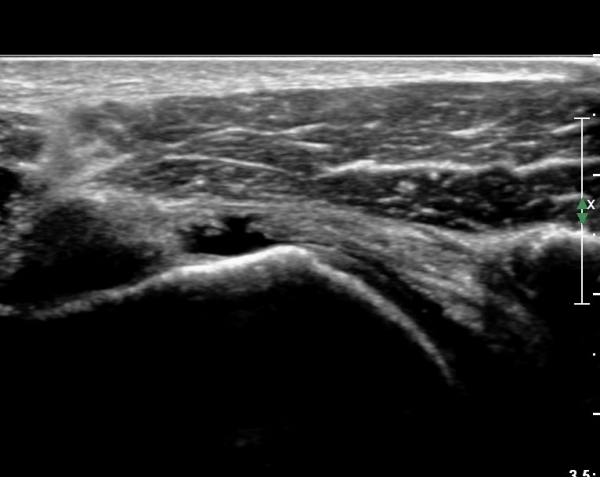

°ß°©ÇÏ±Ù°Ç »óºÎ Á¾´Ü¸é°Ë»ç¿¡¼­ °ß°©ÇϱٰǠ ÆÄ¿­ÀÌ ¶Ñ·ÈÇÔ(»çÁø 4, 5).

°ß°©ÇÏ±Ù°Ç ÁߺΠÁ¾´Ü¸é°Å»ç¿¡¼­ ÈûÁÙÀÌ ¾ã°Ô º¸¿© ÆÄ¿­·Î ÃÊÁ¤µÊ(»çÁø 7).